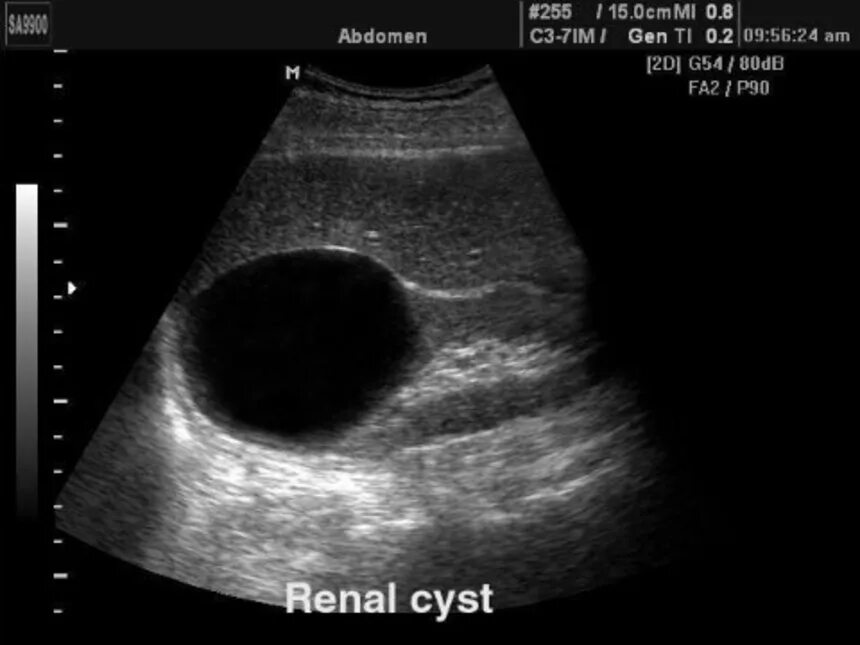

Узи шип